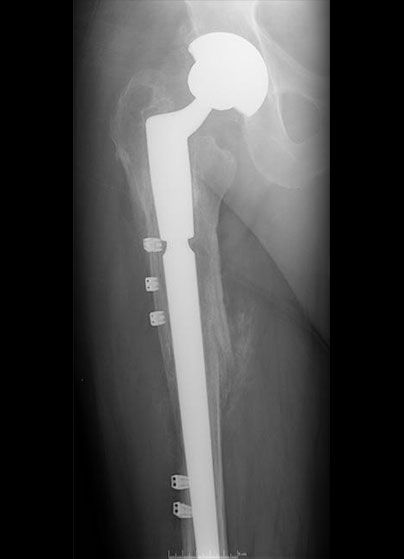

Revised THR